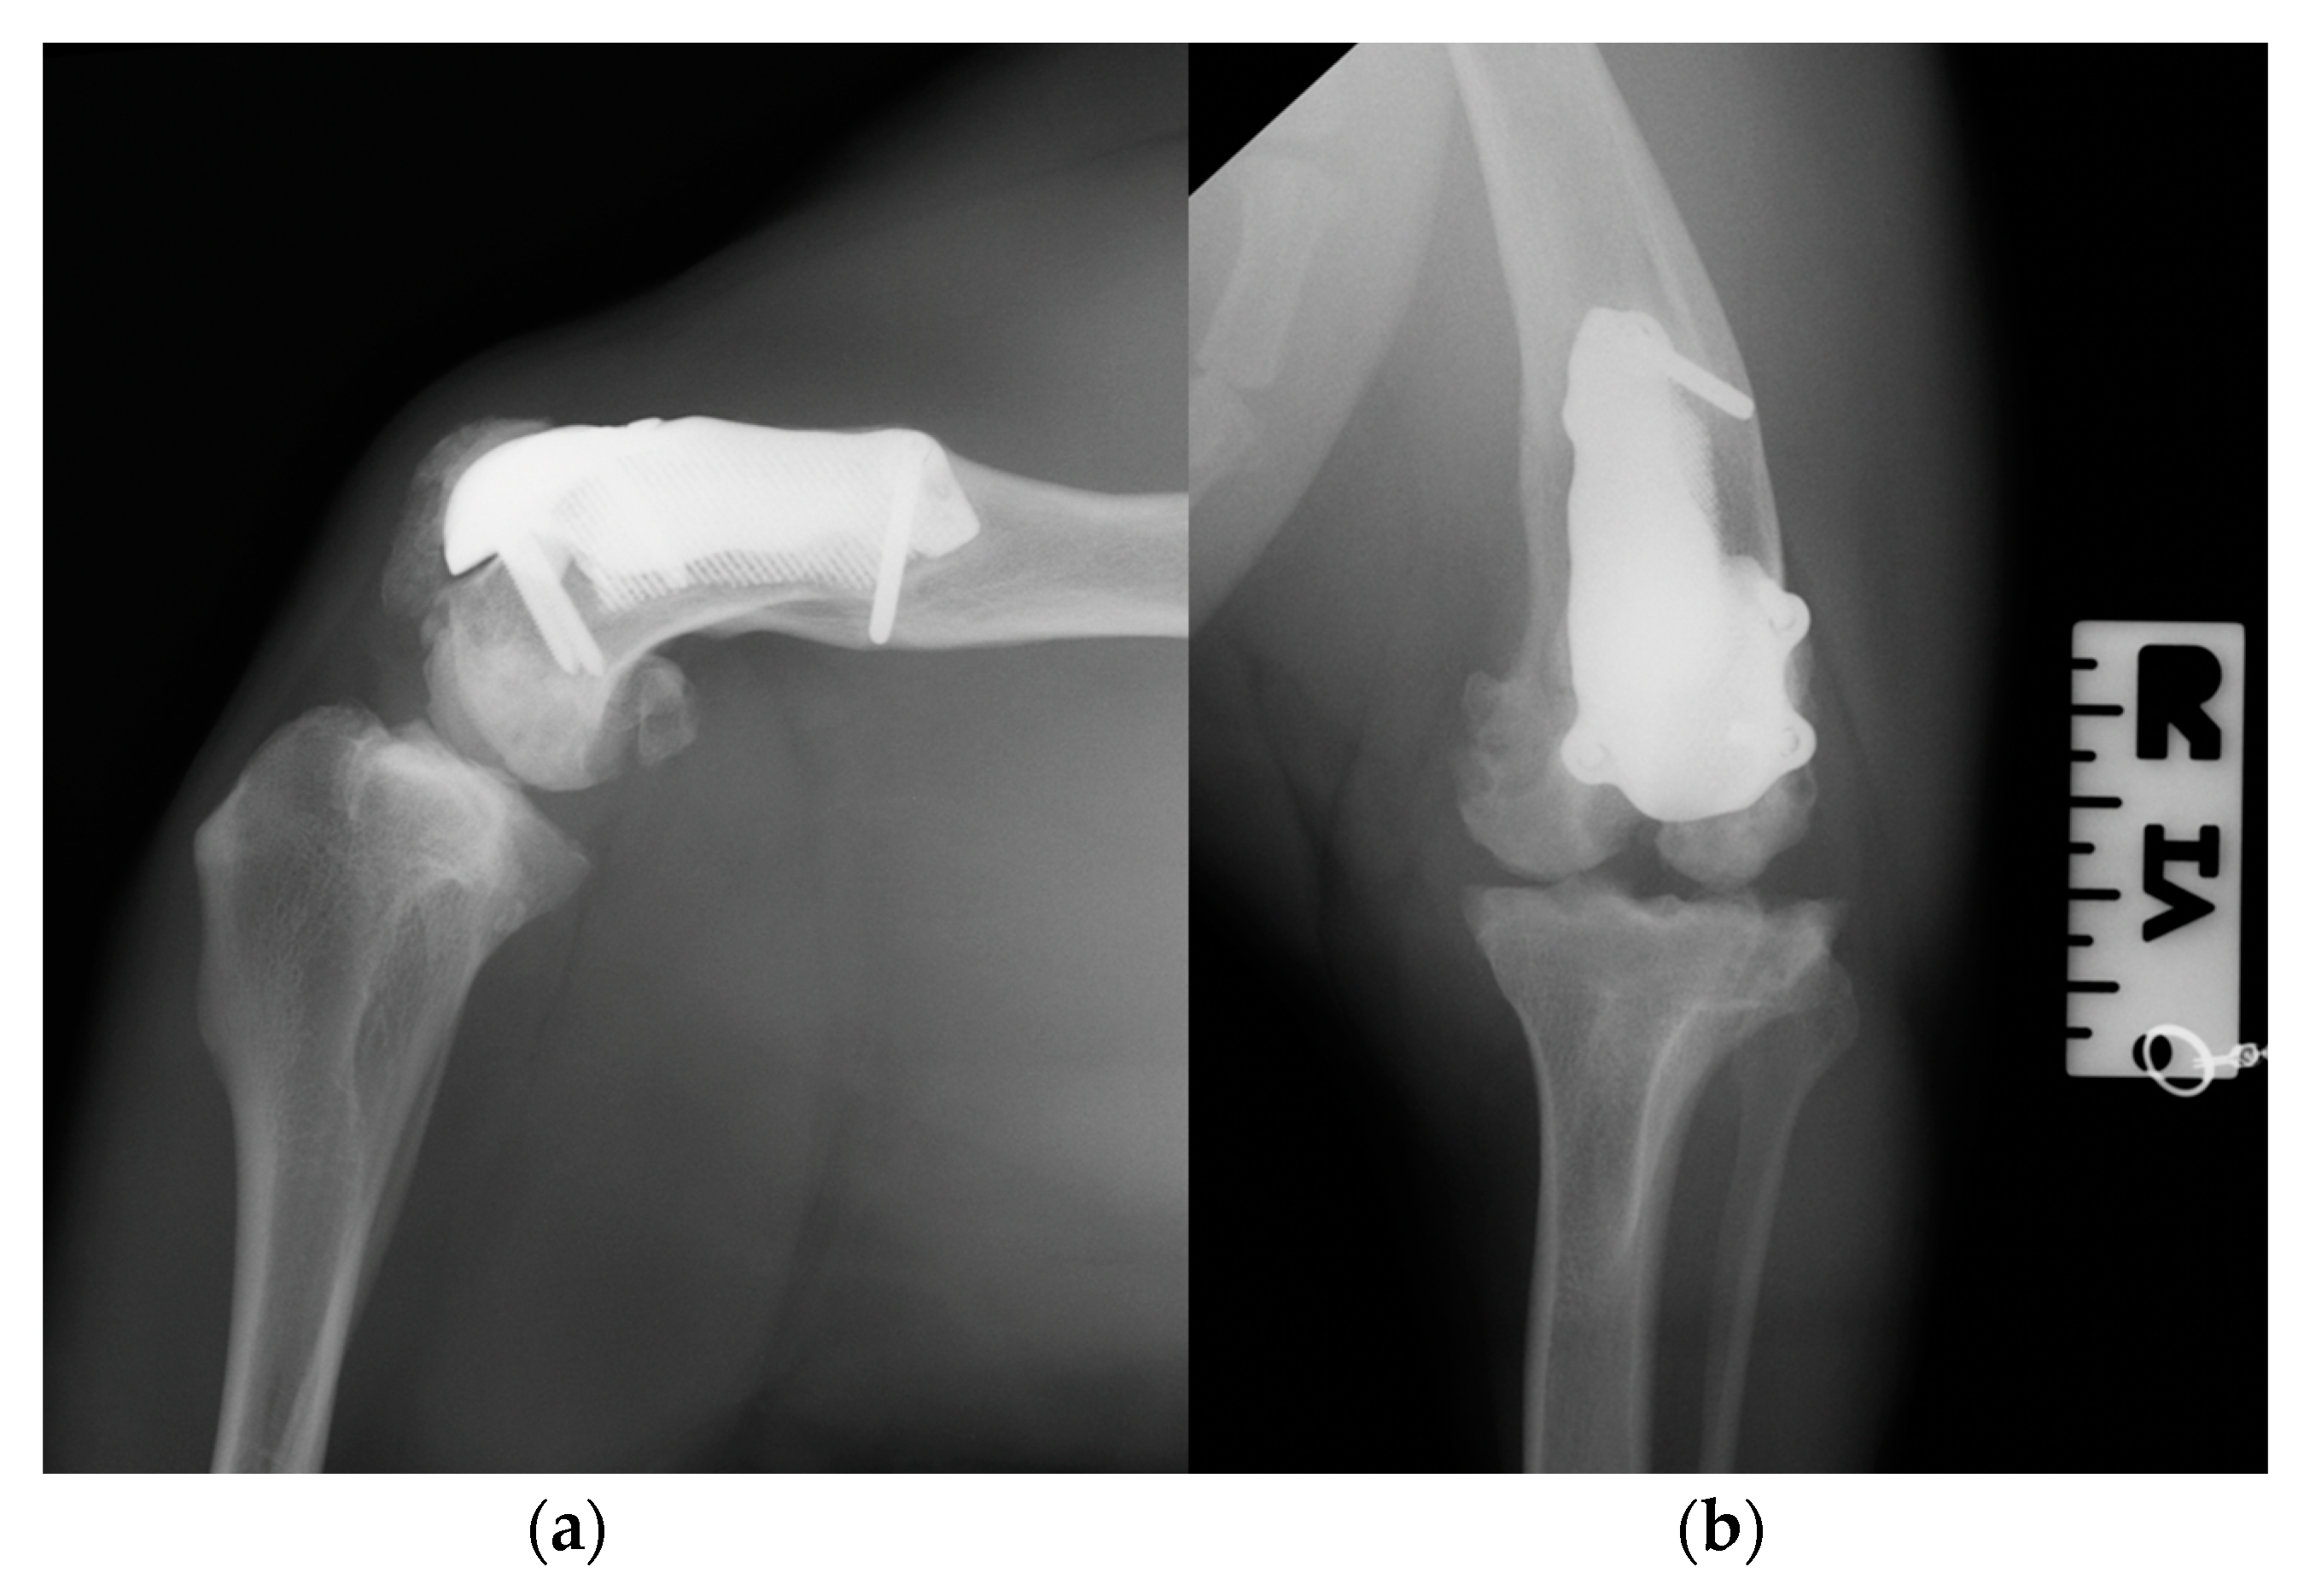

At the 3-month postoperative follow-up, the orthopedic, radiographic and tomographic examination were repeated. The patient showed a grade II right hind limb lameness (on a scale from 0 to IV) [19] (Video S3b). On stifle joint palpation and manipulation, crepitus persisted. The arthralgia and capsular ectasia decreased compared to the postoperative follow-up, and mild pain was elicited upon palpation of the patellar ligament. The estimated angle of extension and flexion of the right stifle was 150–90°, respectively. The radiographic and tomographic evaluations revealed the absence of implant-associated complications, such as implant loosening and migration, a thickening of the patellar ligament, signs of suspicious desmitis and mild osteoarthritic progression at the distal pole of the patella (Figure 11).

At the 6-, 12- and 18-month follow-up (Video S3c), the orthopedic evaluation revealed crepitus, but a grade 0 right limb lameness and absence of patellar ligament desmitis and palpation of the right stifle joint did not elicit pain. The estimated angle of extension and flexion of the right stifle was 160–80°, respectively, while the ROM of the contralateral healthy limb was 160° in extension and 40° in flexion. The thigh circumference of the pathologic limb was 40 cm compared with 47 cm of the healthy one. The radiographic images showed a good osseointegration of the implant and progression of degenerative changes in the distal pole of the patella (Figure 12).

Figure 11. Three-month postoperative medio-lateral (a) and caudo-cranial (b) radiographs of the stifle joint showing the absence of implant-associated complications, such as implant loosening and migration, a thickening of the patellar ligament and mild osteoarthritic changes in the distal pole of the patella compared to postoperative radiographs.

Figure 12. Twelve-month postoperative medio-lateral (a) and caudo-cranial (b) radiographs of stifle joint showing a good osteointegration of the implant and osteoarthritic changes in the distal pole of the patella compared to postoperative and 3-month postoperative radiographs.